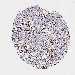

CANCER BREAST CANCER Show tissue menu

BRCA TCGA BRCA VALIDATION PROTEIN EXPRESSION